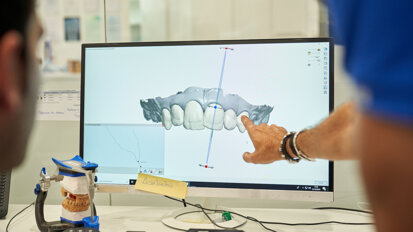

Współdziałanie specjalistów różnych dziedzin w diagnostyce i planowaniu leczenia jest obecnie najbardziej pożądaną formą działania lekarzy dentystów w leczeniu implantoprotetycznym. Współpraca chirurga i protetyka już na etapie planowania leczenia chirurgicznego pozwala na dostosowanie położenia implantu względem przyszłego uzupełnienia protetycznego poprzez wykorzystanie zaprojektowanego uprzednio woskowania. Unikamy w ten sposób sytuacji, gdzie osadzenie ostatecznej pracy protetycznej uzależnione jest od położenia wcześniej wszczepionego implantu. Mając do dyspozycji możliwość przeniesienia woskowania z ust pacjenta do wirtualnej rzeczywistości dzięki dedykowanemu oprogramowaniu, projektowanie odpowiedniego szablonu do zabiegu implantacji staje się dużo łatwiejsze. W świetle takich rozważań, sukces w leczeniu zależy od szczegółowego i przemyślanego doboru pacjentów, wyboru odpowiedniego planu leczenia i wielospecjalistycznego przygotowania pacjenta.

W niniejszym artykule opisano zastosowanie 2 różnych możliwości oprogramowania: CS 3D Imaging Software, które pozwala na trójwymiarową ocenę diagnostyczną, wykonanie rekonstrukcji wybranego obszaru bez nakładania się struktur anatomicznych oraz na dokonanie pomiarów wyrostka zębodołowego przed planowanymi zabiegami implantologicznymi oraz oprogramowaniem DDS-PRO Implants. Przeznaczone jest ono do wsparcia procesu diagnostycznego, przygotowania do zabiegu implantologii stomatologicznej, wizualizacji 3D struktur kostnych oraz zaplanowania i symulacji zabiegu. Technika ta wykorzystuje dane z tomografii komputerowej wiązki stożkowej8 i umożliwia wykonanie specjalnej pokrywy na zęby o zadanej grubości, zwanej szablonem chirurgicznym lub prowadnicą wiertniczą, dzięki możliwości drukowania modelu z DDS-Pro w drukarce 3D. W miejscach, gdzie umieszczany będzie implant, prowadnica wiertnicza posiada nadlewy z otworem, w którym umieszczana jest tuleja wprowadzająca wiertło.

Do wykonania szablonu chirurgicznego wykorzystano oprogramowanie DDS-PRO, które umożliwia bezpośrednie przenoszenie woskowania do obrazowania 3D.

W pierwszym prezentowanym przypadku zastosowano oprogramowanie DDS-PRO. Umożliwia ono bezpośrednie przenoszenie woskowania do obrazowania 3D badanych struktur oraz wykonanie szablonów chirurgicznych do zabiegu implantacji z uwzględnieniem każdego systemu implantologicznego. Wygenerowana przy użyciu drukarki 3D prowadnica wiertnicza zapewnia pożądaną dokładność wykonania otworów w kości oraz wysoką precyzję dostosowania położenia implantu względem przyszłego uzupełnienia protetycznego, co potwierdzają dane piśmiennictwa.9-13 Także w opisanym przypadku wykorzystanie szablonu chirurgicznego zapewniło powodzenie zaplanowanego leczenia.